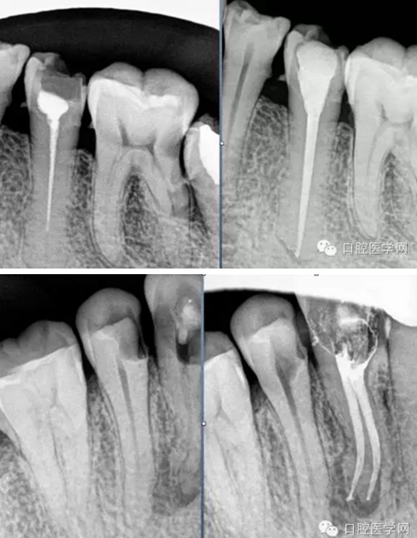

根充(從術(shù)后X光片可以看出根管充填完整,專業(yè)上叫恰充)

根充其實很簡單,只要前面的預備做好了,后面的充填就很順利,試尖恰好,AH樹脂湖劑+大準度牙膠充填,平齊根管口將牙膠截掉,冷充的話就結(jié)束了。若要做熱充,將攜熱器頭對準牙膠的中央,加熱3-4秒迅速壓入需要截斷的部位,然后等十幾秒待攜熱器桿冷卻后再加熱1-2秒取出牙膠,最后將熱牙膠注入,邊注邊壓,嚴密充填,結(jié)束。暫封一周后冠修復。通過這樣的操作牙齒就不可能發(fā)生再次感染和疼痛了。

常用標準:恰充,三維致密,流暢,錐度流暢一致。

但臨床上很難從X-ray上評價一個真正的標準的根管充填。組織學的檢驗才是金標準。幾年的追蹤,前后的對比,這些都很重要。 所以我們不能說這個牙我給你做了根管治療就一輩子沒事了,即使你按標準的程序操作,一些復雜的根管系統(tǒng)是我們不能控制的。

臨床病例分享:

有什么樣的標準就有什么樣的技術(shù)